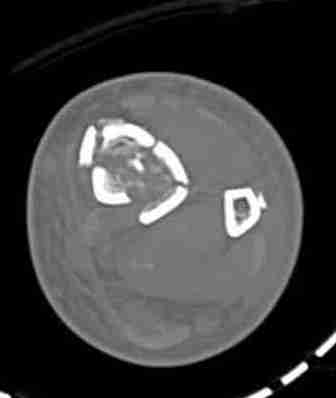

Сравнительный повторный мониторинг на компартмент синдром, на голени утром давление поднялось до 70 мм, когда послеоперационные были около 30мм.

Срочная фасциотомия на всех 4 компартментах: латерально и медиально,

кстати было достаточно только латеральной фасциотомии, чтобы услышать на допплере пульсацию,

В настоящее время больной в реанимации по поводу Черепно Мозговой Травмы и состояние улучшается. Запланировал ушивание раны в пятницу, если позволит состояние мягких тканей и при отсутстви отека возможно удастся просунуть перкутанномедиальную пластину.

КТ пилона имеем.